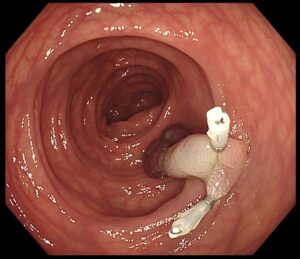

✔ まずクリップでポリープの茎をしっかり把持し、血流を遮断(写真2,3)

(写真2)